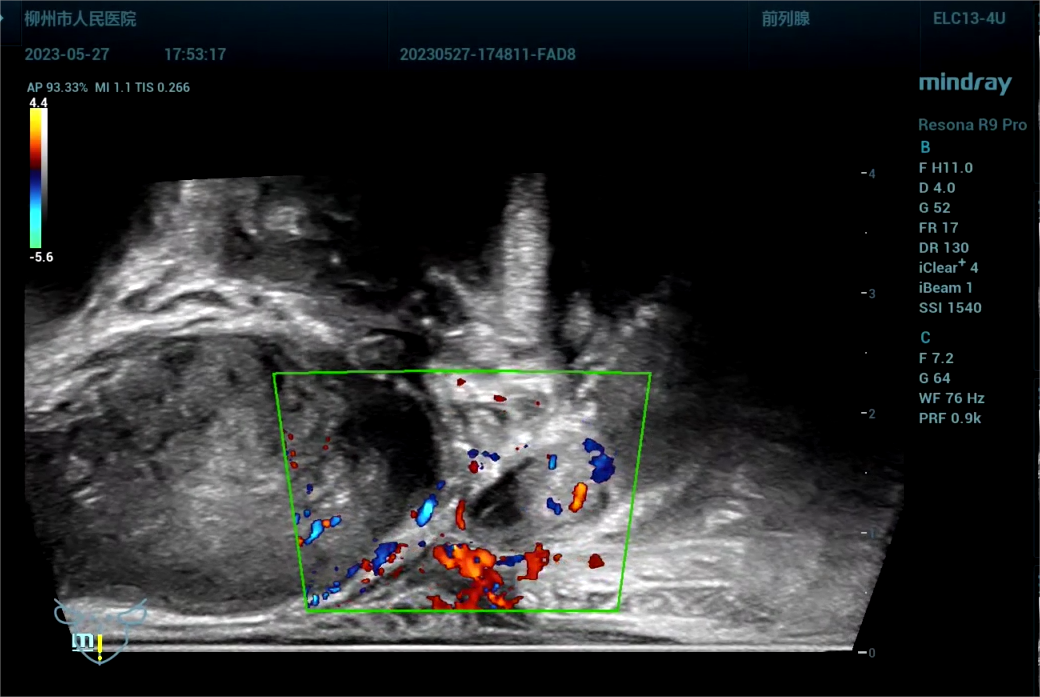

病史为,30岁年轻男性,主诉为反复尿痛2年余。临床诊断是尿路感染。

443081 截取视频 截取视频 截取视[00_24_56][20230614-071830].png